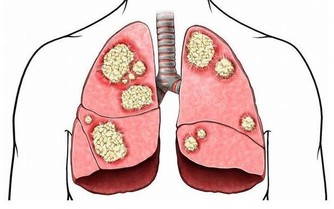

臉色

如果最近臉色不好,臉頰髮灰,說明你的身體缺氧,肺部功能不太好。最好多去公園散步、慢跑,再補充點綠色蔬菜,增加蛋白質、礦物質和粗纖維的攝入。